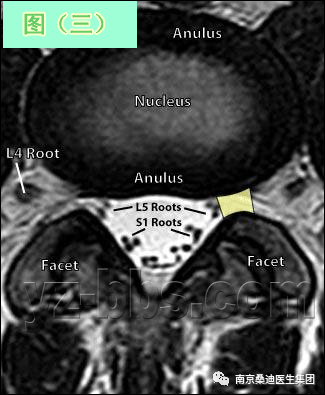

图(三)是另一个健康的45岁男性的L4椎间盘的轴状面观。 现在我们可以区分开髓核区及周围的纤椎环区。注意,在此平面将看不到“米老鼠”。另外请注意靠近L5神经根的椎间盘后缘的凹度,这是正常健康椎间盘的象征。L4发出神经根更靠侧方一点。这就不难理解为什么如果有大的椎间盘突出或椎管狭窄,发出神经根L4及过往神经根L5将同时受压。 在此图中,可清楚地看到悬挂在硬膜囊内的细小的神经根(L5神经根及S1神经根),它们以不完全有绪地状态排列着。 注意,神经孔是很开阔的(浅黄色区),表明没有因邻近椎间关节问题形成在的椎管狭窄。T2加权象对于察看退化性椎间盘病是最好的,因为T2像将富含水份的结构表现为亮白色, 含水少的区域表现为黑色。